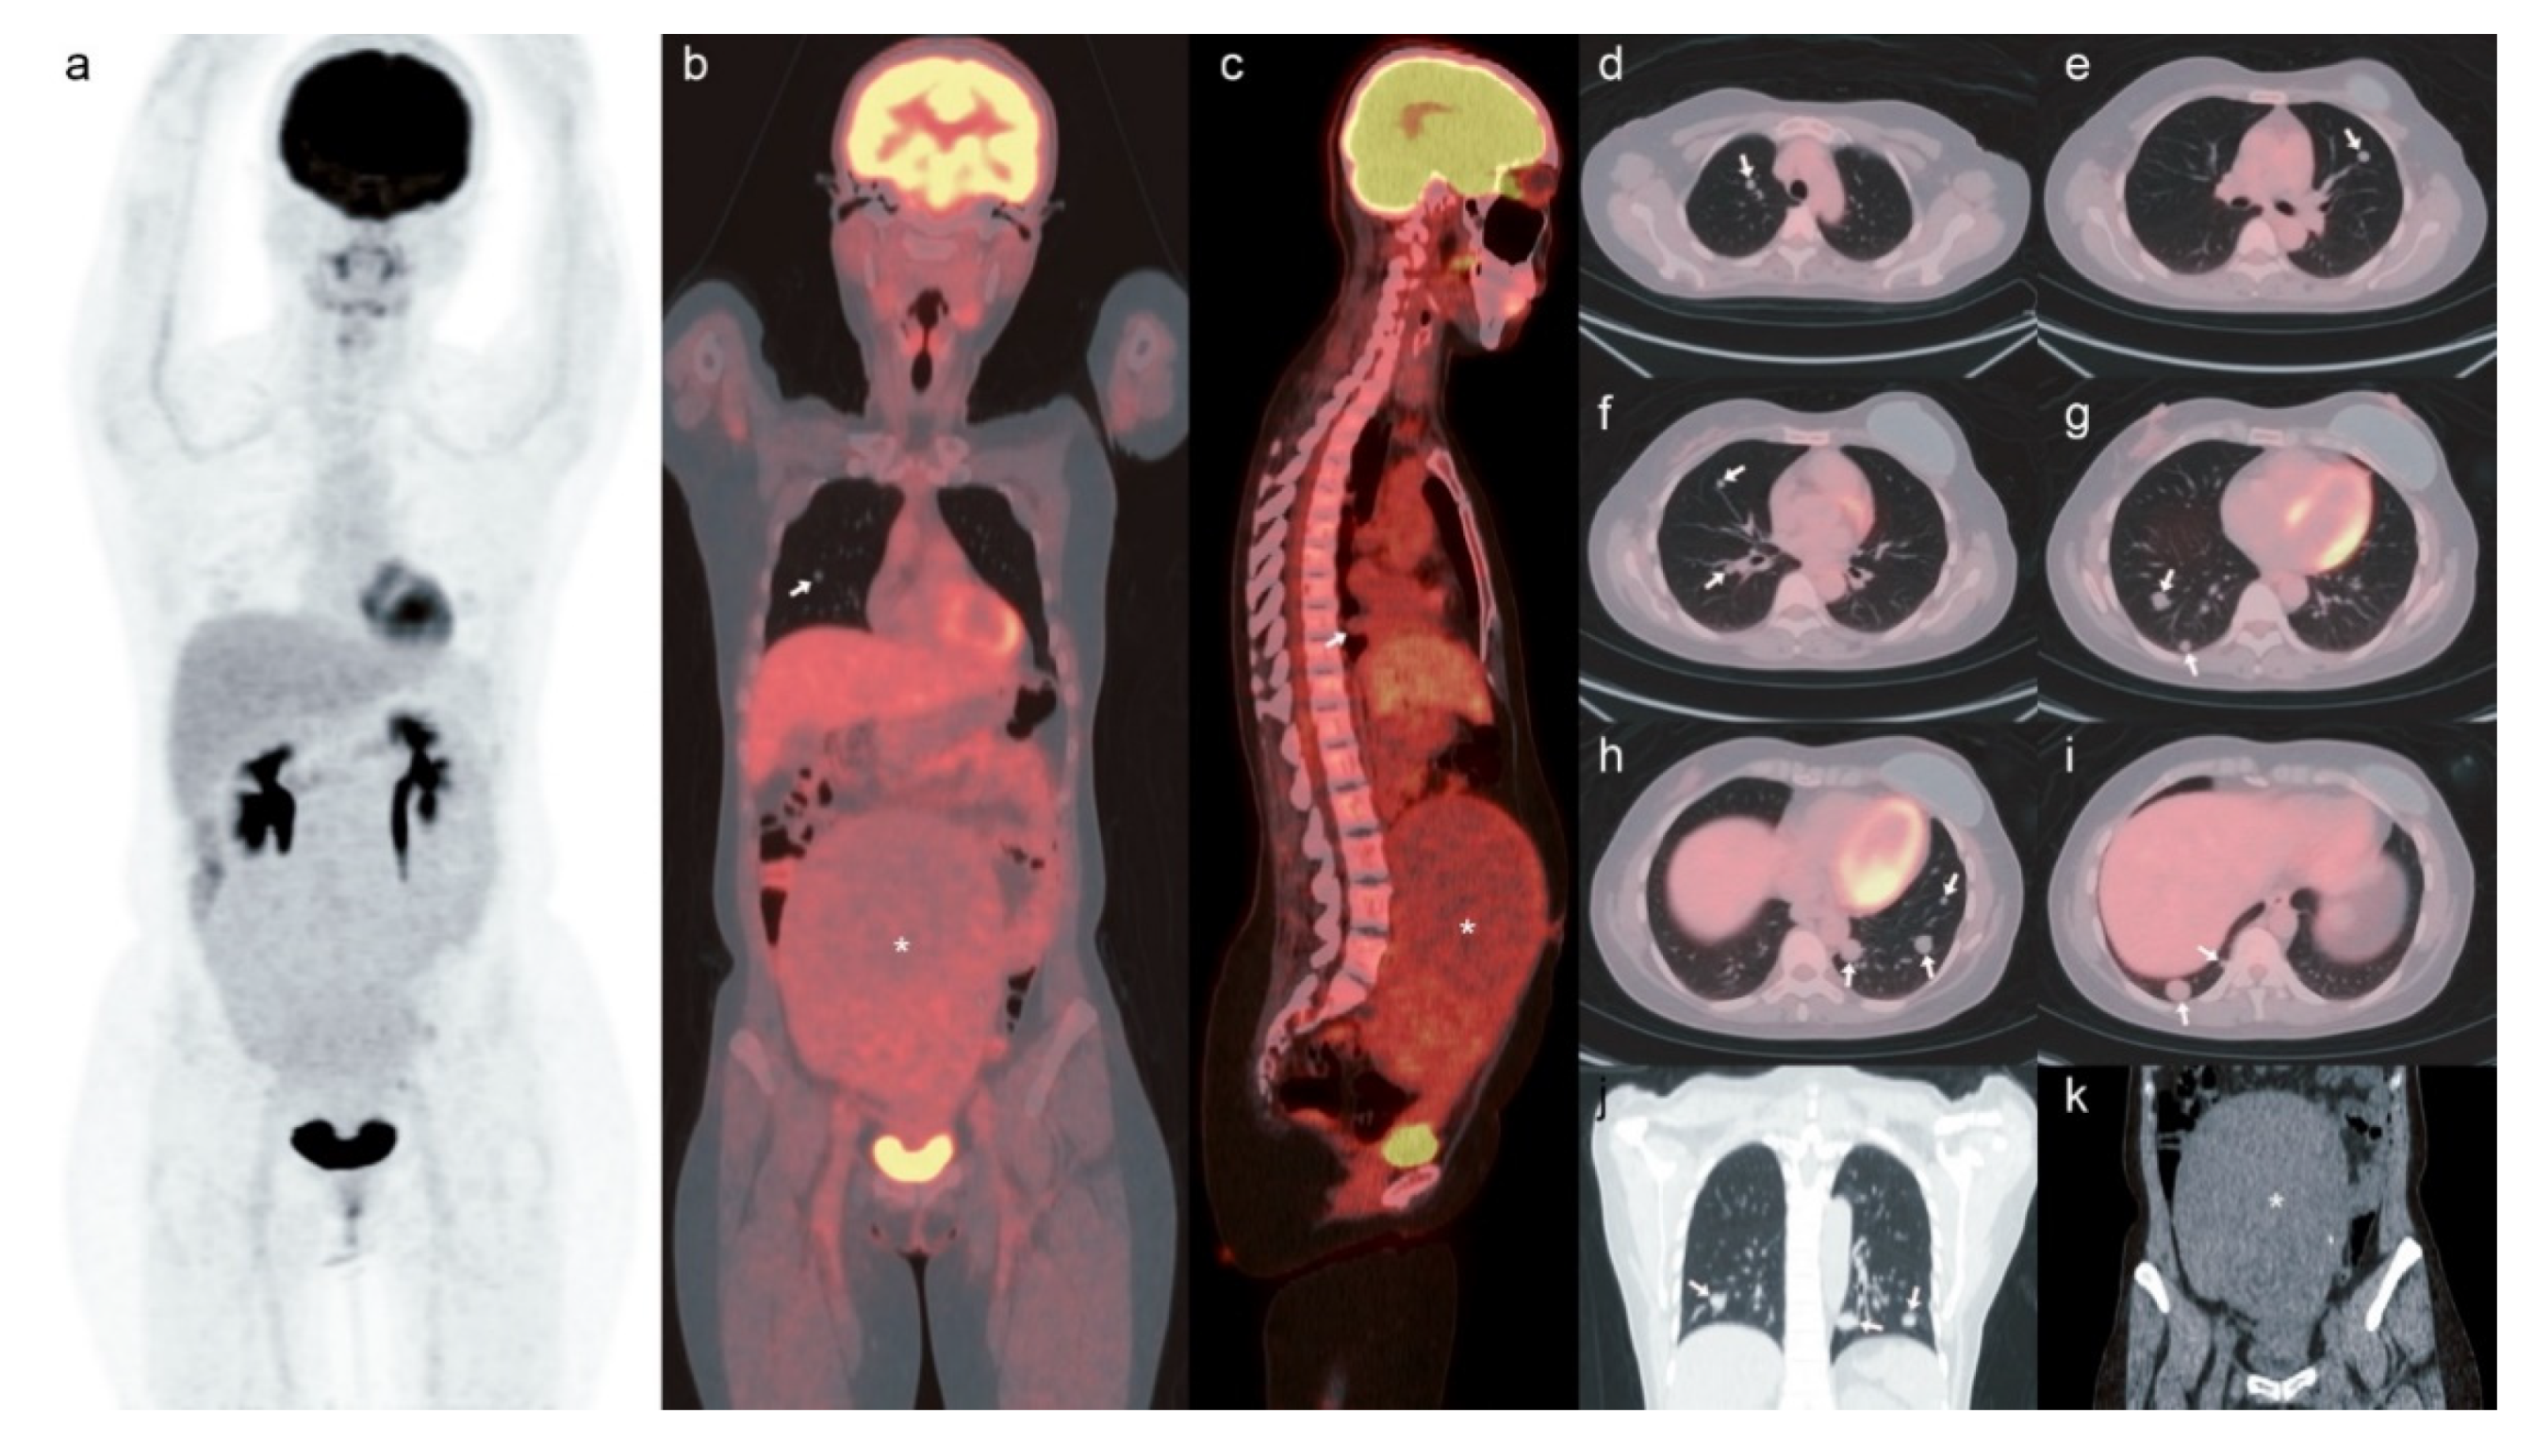

Our case was a 49-year-old woman with a history of invasive ductal carcinoma of the left breast, pT1aN1a, cM0, estrogen receptor (ER)-positive; progesterone receptor (PR)-positive; human epidermal growth factor receptor 2 (Her2)-negative. She underwent left nipple-sparing mastectomy and adjuvant chemotherapy with epirubicin, cyclophosphamide and docetaxel. One year after the treatment, her chest radiography and CT revealed multiple bilateral pulmonary nodules, suspected breast cancer with pulmonary metastasis. An [18F]-FDG PET/CT scan was performed for tumor restaging (Figure 1). The maximum intensity projection image and fused PET/CT showed faint and non-FDG avid nodules in the lungs with the maximum size being 1.7 cm over the right lower lobe, and a maximum standardized uptake value (SUVmax) of 1.3. Additionally, a large mass about 19 × 16 cm2 in size arising from the uterus with calcified spots occupying the abdominal cavity depicting mild FDG uptake was observed, with an SUVmax 2.2, suggestive of uterine fibroids. Benign metastasizing leiomyomas (BML) in the lung were first impressed.

Figure 1.

Whole-body [18F]-FDG PET/CT scan. The (a) maximum intensity projection image and the (b) coronal view, (c) sagittal view, (d–i) axial view of fused PET/CT showed faint and non-FDG avid nodules in the lungs (shown by arrows). (j) Coronal view of chest part, attenuation correction CT revealed multiple nodules (shown by arrows) with maximum size of 1.7 cm over the right lower lobe, and maximum standardized uptake value (SUVmax) of 1.3. (b,c) and (k) Coronal view of abdominal part, attenuation correction CT showed a huge mass about 19 × 16 cm2 in size arising from uterus with calcified spots occupying the abdominal cavity depicting mild FDG uptake, SUVmax 2.2 (shown by asterisk).